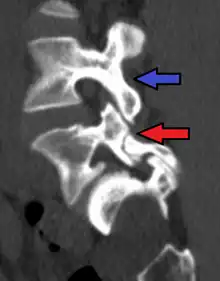

Anterolisthesis L5/S1. Blue arrow normal pars interarticularis. Red arrow is a break in pars interarticularis.

Isthmic anterolisthesis is where there is a defect in the pars interarticularis (spondylolysis).[15] It is the most common form of spondylolisthesis; also called spondylolytic spondylolisthesis, it occurs with a reported prevalence of 5–7 percent in the US population. A slip or fracture of the intravertebral joint is usually acquired between the ages of 6 and 16 years, but remains unnoticed until adulthood. Roughly 90 percent of these isthmic slips are low-grade (less than 50 percent slip) and 10 percent are high-grade (greater than 50 percent slip).[13] It is divided into three subtypes:[16]

- Isthmic anterolisthesis (also called type 2) is caused by a defect in the pars interarticularis (spondylolysis) but it can also be seen with an elongated pars.[11][12]